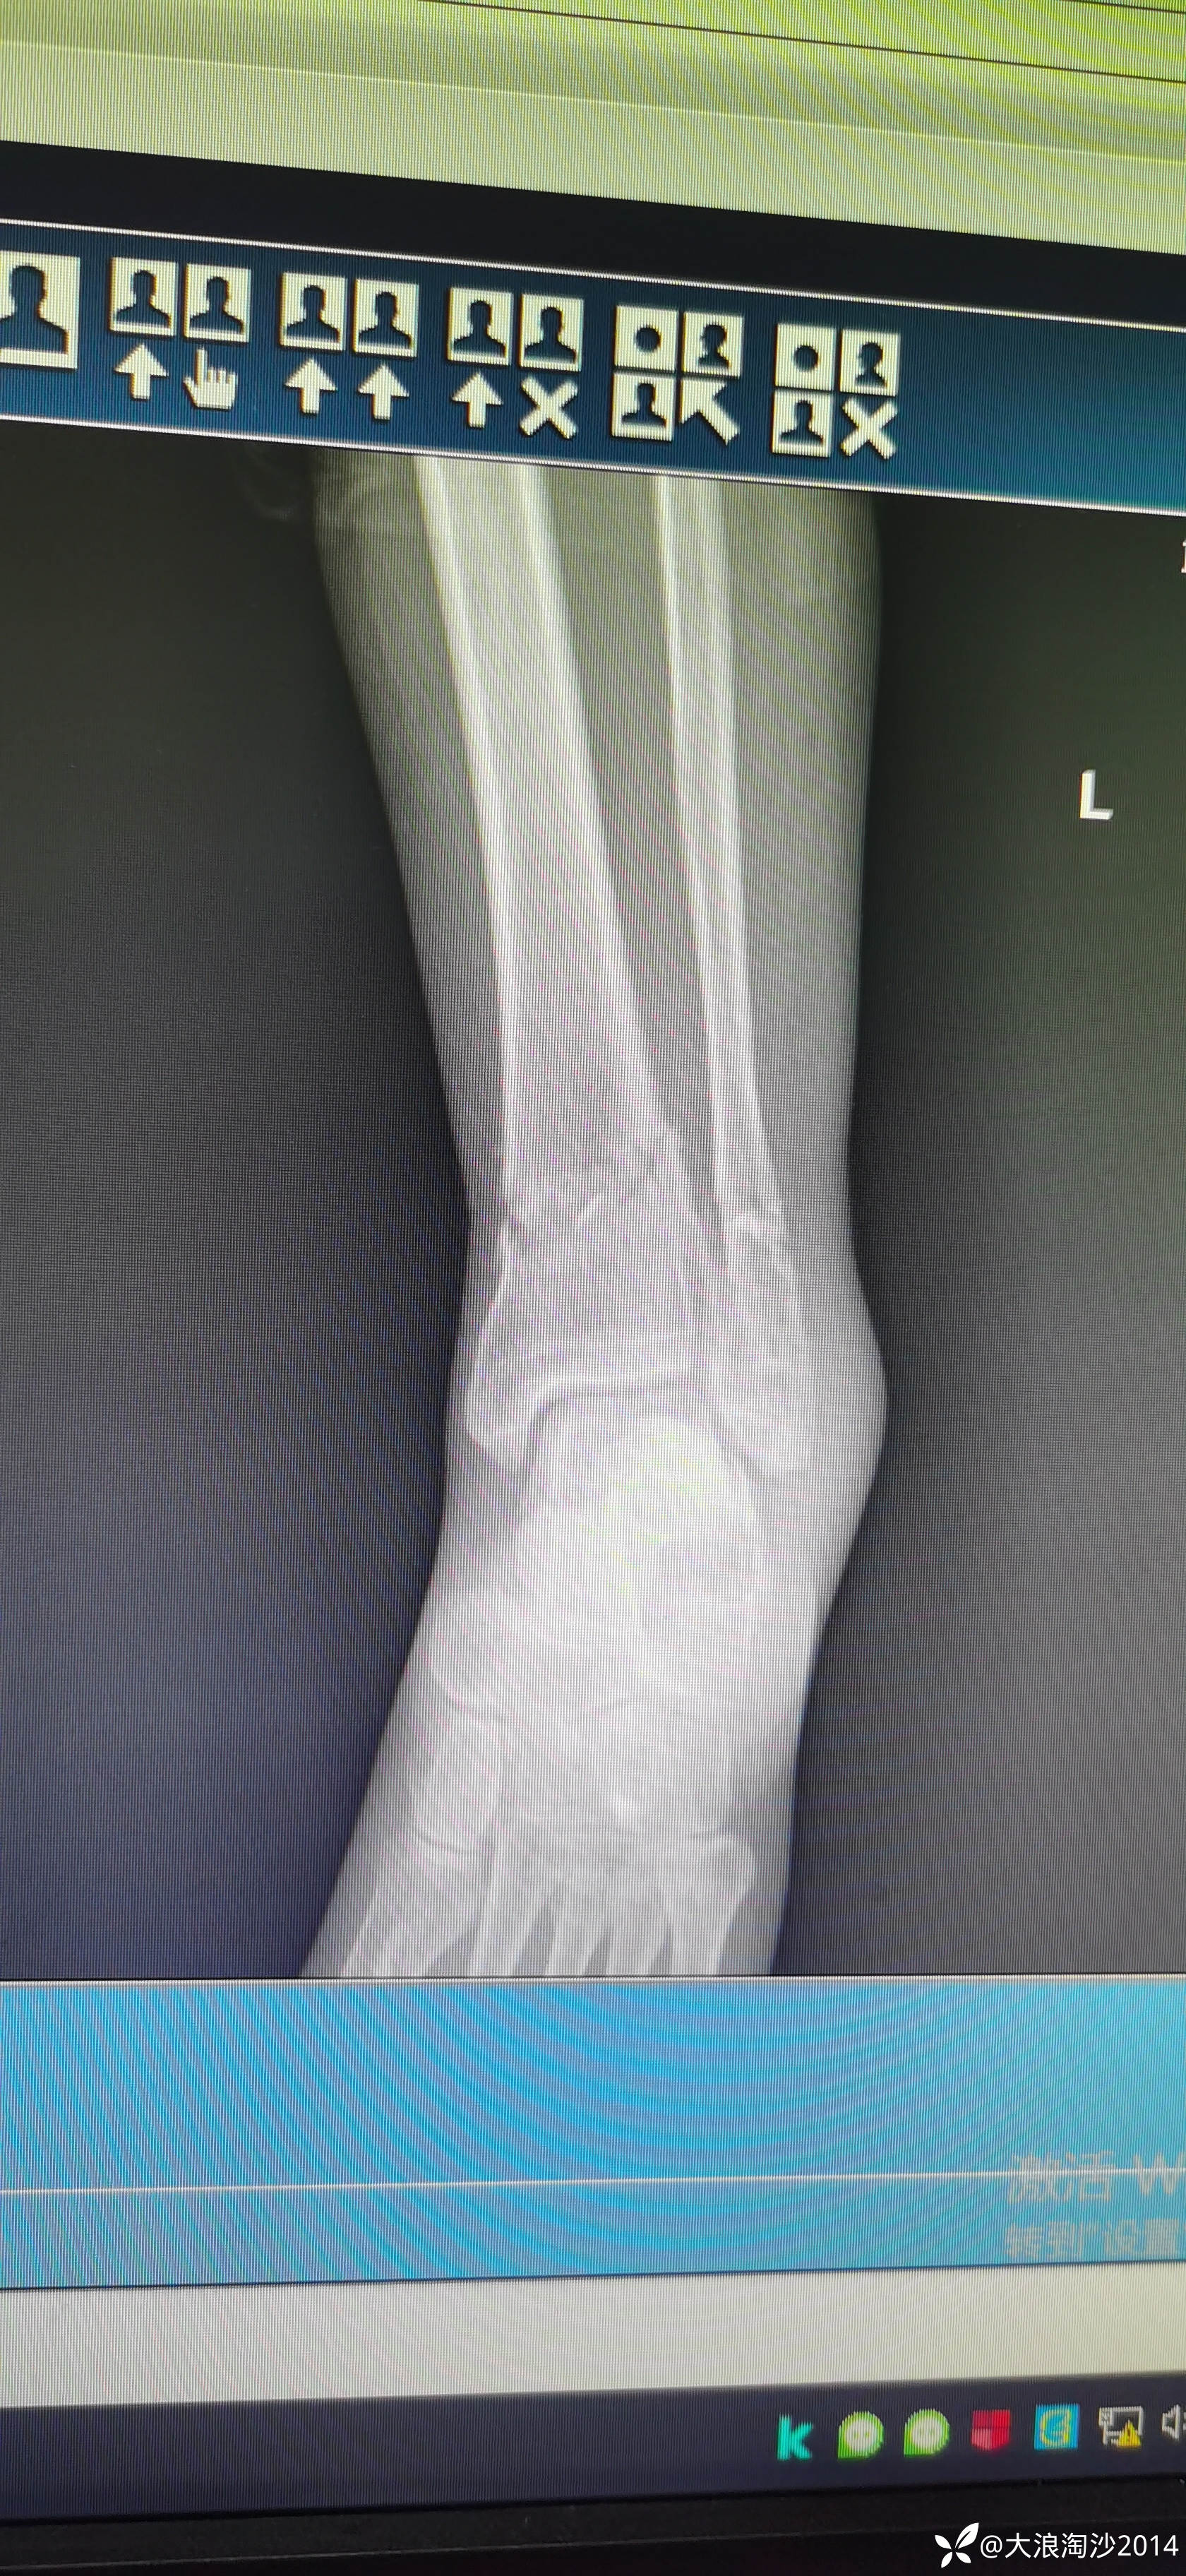

一65岁女性患者,偏瘦,体重75斤,车祸外伤致左胫腓骨远端骨折,入院后消肿后,病人可以用皮包骨头形容,考虑胫骨远折端不适合用内侧插板(mippo技术),病人太瘦,如取两个切口分别处理胫腓骨,切口容易出现问题,因此采用前外侧一个切口处理胫腓骨远端骨折(片子顺序上传有点乱)